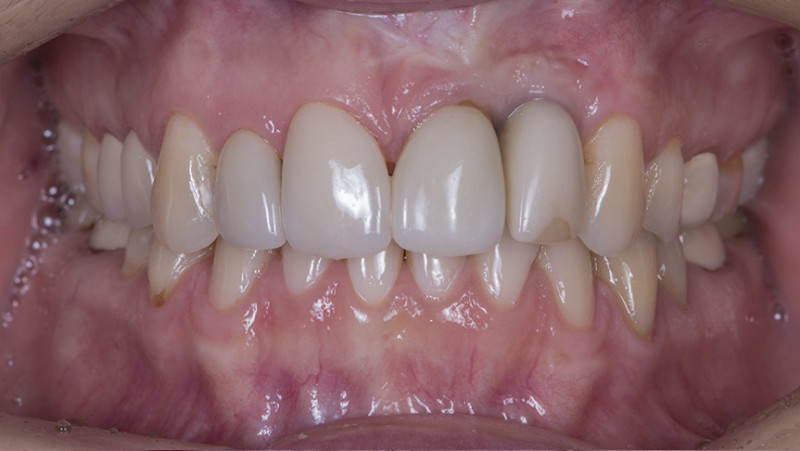

Установка коронки на зуб

Провели швейцарскую профгигиену. Перелечили зубы с несостоятельными пломбами и воспалениями. Удалили зубы в боковом отделе с одномоментной имплантацией и пластикой десны. Установили временные коронки. После приживления имплантатов установили постоянные коронки из диоксида циркония на зубной ряд нижней и верхней челюсти.